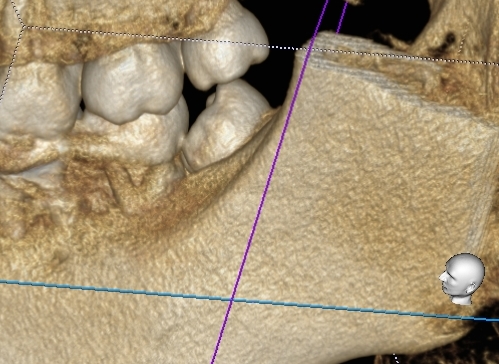

本日は親知らずを抜歯前にCT精密検査を行って抜歯したご報告です。

上記画面向かって右側下の横向きに生えた親知らずです。

以下にCT画像です。

今回はわかりやすい画像を添付致しましたが、これ以外に神経との近接がどの程度か、また根っこがどのような形をしているのかなど事前に多くの情報が得られます。